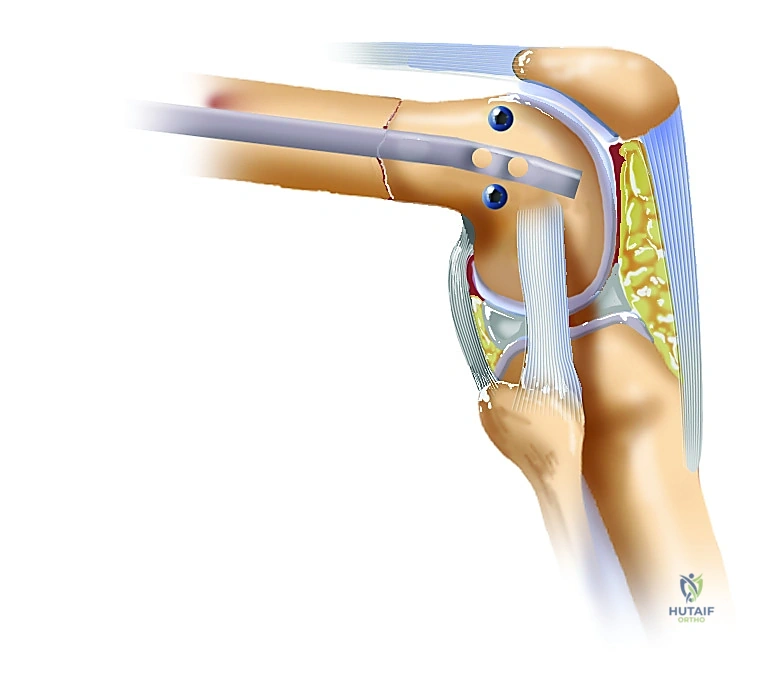

تُعد "نقطة الدخول" (Entry Point) هي حجر الزاوية والخطوة الأكثر حساسية في عملية المسمار الارتدادي. إذا تم تحديد هذه النقطة بشكل خاطئ، فقد يؤدي ذلك إلى تلف الغضروف المفصلي، ألم مزمن في الركبة، أو عدم استقامة العظم بشكل صحيح.

يتم تحديد نقطة الدخول بدقة متناهية في الطرف السفلي من "الأخدود الرضفي الفخذي" (الجزء الأمامي من الركبة الذي تنزلق عليه عظمة الصابونة). وتحديداً، تقع هذه النقطة في الثلم بين اللقمتين (Intercondylar Notch)، أمام نقطة اتصال الرباط الصليبي الخلفي (PCL) مباشرة.

من الناحية الإشعاعية (باستخدام جهاز الأشعة السينية داخل غرفة العمليات - Fluoroscopy)، يحرص الأستاذ الدكتور محمد هطيف على تحديد هذه النقطة بدقة بالغة. في المنظر الأمامي الخلفي (AP)، تقع النقطة في خط الوسط تماماً بين اللقمتين. أما في المنظر الجانبي (Lateral)، فتكون أمام "خط بلومنسات" (Blumensaat's Line) مباشرةً.

لماذا هذه النقطة تحديداً؟ هذه المنطقة المفصلية مسطحة نسبياً ولا تلامس الرضفة (الصابونة) أثناء الحركة العادية إلا عند ثني الركبة بزاوية تتجاوز 120 درجة. وبالتالي، فإن إدخال المسمار من هذه النقطة يقلل إلى الحد الأدنى من خطر الإضرار بالغضروف المفصلي الحساس، مما يقي المريض من آلام الركبة المستقبلية أو خشونة المفصل المبكرة.

* في الجزء السفلي والركبة: يمر الشريان المأبضي (Popliteal Artery) والعصب الظنبوبي خلف الركبة مباشرة. الحفاظ على مسار الأدوات الجراحية داخل العظم بدقة يمنع أي اختراق غير مقصود للمنطقة الخلفية للركبة، مما يحمي هذه الأوعية الحيوية.